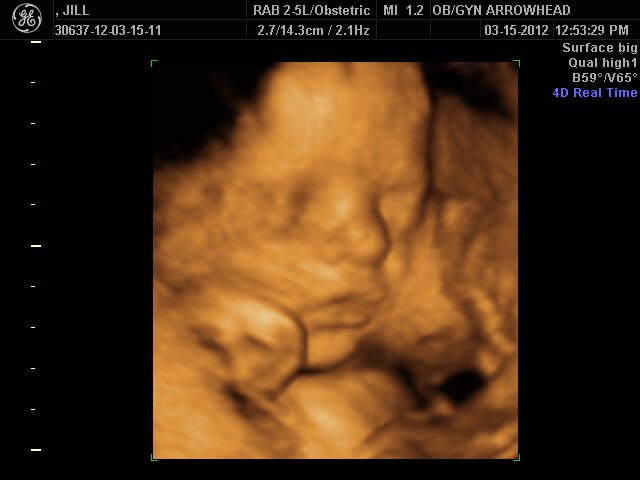

We offer complimentary 3D/4D Ultrasounds to all our OB patients around 30 weeks! The following photos are some examples of our work, shown with permission from our patients.